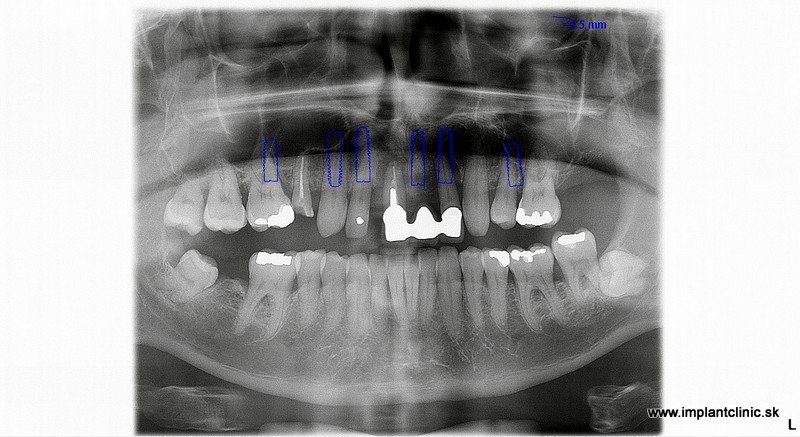

Na základe RTG a CT vyšetrenia náš hlavný implantológ MUDr. Marek Salka, odporučil pacientovi extrakcie nevyhovujúceho chrupu a následne celkovú rekonštrukciu hornej a dolnej čeľuste pomocou zubných implantátov s fixným keramickým oblúkom do vrchnej čeľuste a náhrada stoličiek v dolnom chrupe pomocou zubných implantátov a estetická úprava ostatných zubov pomocou zubných koruniek.

Plán ošetrenia pacienta Jakuba, a teda celková rekonštrukcia jeho chrupu, zahŕňal implantáciu 7 zubných implantátov do hornej čeľuste a 3 zubné implantáty do sánky. V spodnej čeľusti mal pacient na pláne ošetrenia naplánovaných ešte 10 zubných koruniek.

Pred implantáciou sa pacientovi extrahoval zostatkový chrup.